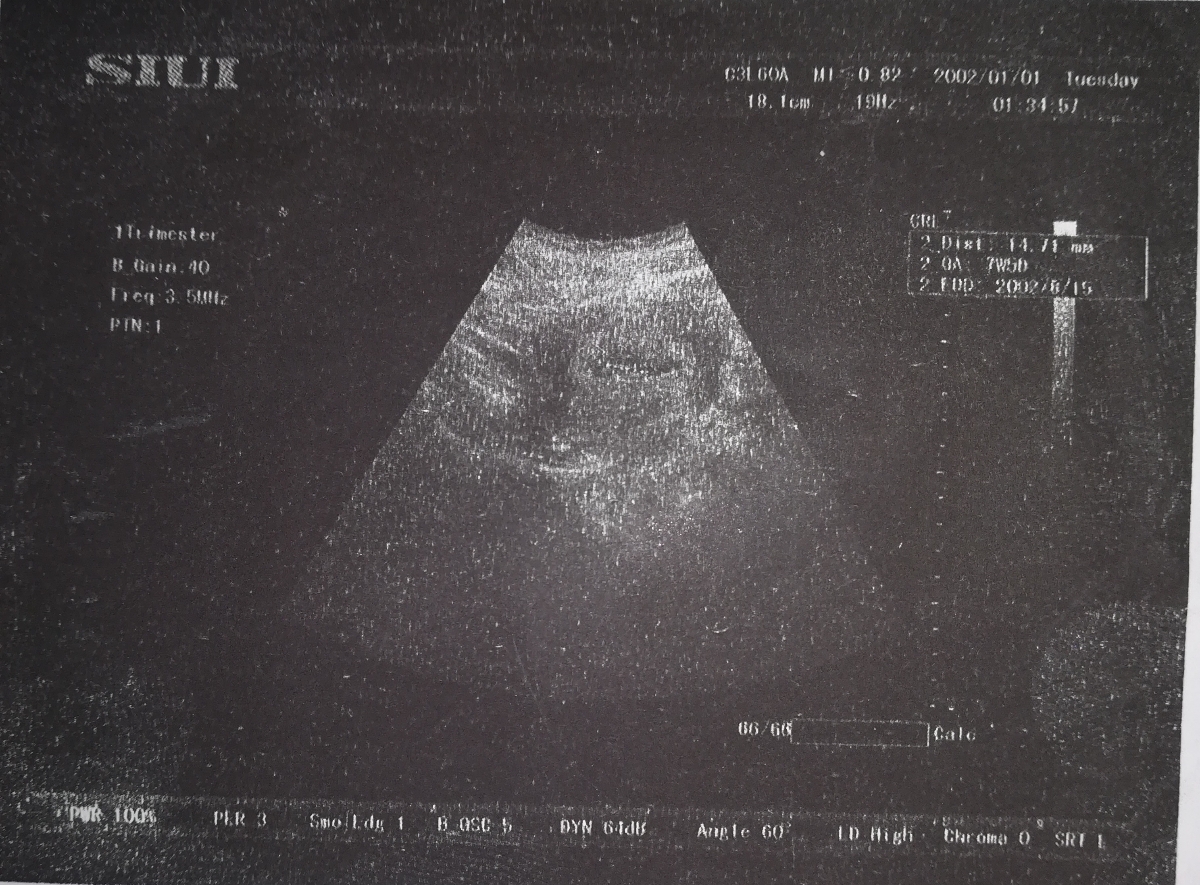

این دوتارو باهم بهم داد چرا داخله یکیش نوشته 7هفته و 5روز داخله یکیش نوشته 8هفته

داخله این سونو مشخصه سمته راسته یا چپ، آخه اون پایین به انگلیسی نوشته راست

نکنه دوتاهست😆😆😆